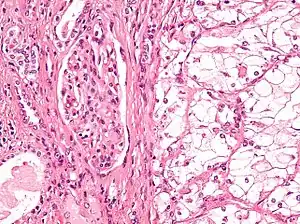

The most common type of kidney malignancy is renal cell carcinoma,[31] which is thought to originate from cells in the proximal convoluted tubule of the nephron.[12][32] Another type of kidney cancer although less common, is transitional cell cancer (TCC) or urothelial carcinoma of the renal pelvis.[33] The renal pelvis is the part of the kidney that collects urine and drains it into a tube called the ureter.[33] The cells that line the renal pelvis are called transitional cells, and are also sometimes called urothelial cells. The transitional/urothelial cells in the renal pelvis are the same type of cells that line the ureter and bladder. For this reason TCC of the renal pelvis is distinct from RCC and is thought to behave more like bladder cancer.[33] Other rare types of kidney cancers that can arise from the urothelial cells of the renal pelvis are squamous cell carcinoma and adenocarcinoma.[12]

Renal cell carcinoma has been further divided into sub-types based on histological features and genetic abnormalities. The 2004 WHO Classification of the Renal Tumors of the Adults describes these categories:[37]